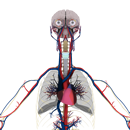

The 3D learning experience places students in virtual environments, allowing them to walk down a street in ancient Rome, visit the outer reaches of the universe or move through the chambers of a beating heart. Read More